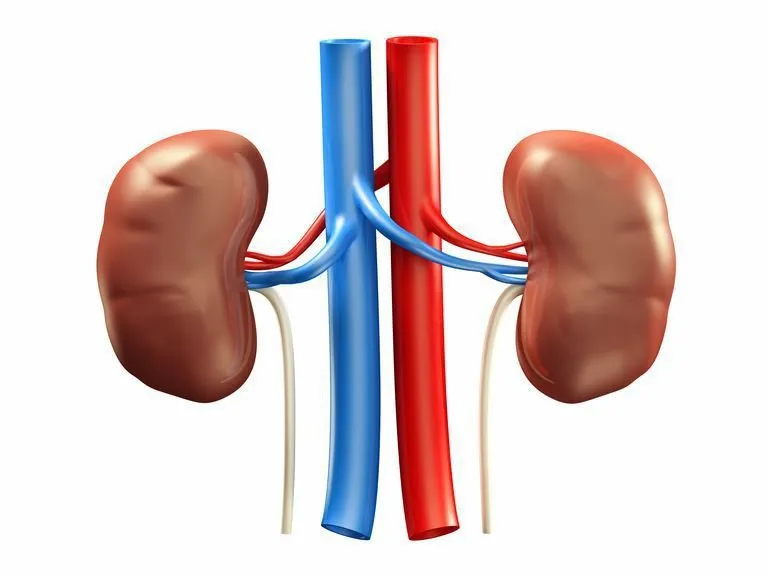

Các dạng hẹp động mạch thận

Hẹp động mạch thận là tình trạng hẹp lòng động mạch thận, làm giảm lưu lượng máu đến thận. Nguyên nhân chủ yếu do xơ vữa động mạch hoặc loạn sản cơ xơ. Bệnh có thể dẫn đến tăng huyết áp, bệnh thận do thiếu máu cục bộ và các vấn đề tim mạch. Phát hiện sớm và điều trị kịp thời rất quan trọng để bảo vệ chức năng thận và cải thiện tiên lượng.